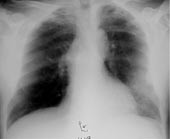

Pasient 5 . 64 år gammel storrøykende mann, som innkom med en tre dagers sykehistorie. Tilstanden hadde startet med ømhet i hypogastriet og frostanfall. Han følte seg kjekk ved innleggelse til tross for 40 ˚C feber, og det kom frem at det var sønnen som hadde tatt initiativ til innleggelsen fordi pasienten var forvirret og hadde talevansker. Han var ikke subjektivt dyspneisk, men arteriell p O 2 (a) var betydelig redusert (<6kPa). Ved klinisk undersøkelse var det spredte basale krepitasjoner bilateralt, og røntgen thorax viste bilaterale fortetninger, mest uttalt i høyre midtlapp. CRP var 233 mg/l, leukocytter 10,7 × 10 9 /l, albumin 24 g/l, natrium 132 mmol/l. Han fikk penicillinbehandling første to døgn, men da det kom frem at han hadde vært på reise til Italia to uker før innleggelse, valgte man fra dag 3 å legge til erytromycin for å dekke opp for legionellapneumoni. På grunn av dårlig behandlingsrespons, økende CRP til 414 mg/l og vedvarende p O 2 (a) på under 6 kPa ble han bronkoskopert, og bronkialskyllevæske ble sendt til legionelladyrking. Det kom oppvekst av Legionella etter to døgn. Han responderte noe tregt på behandling, og man la til rifampicin i kombinasjon med erytromycin. Etter en uke ble han imidlertid afebril og blodgassverdiene normalisert. Det videre forløp var ukomplisert.